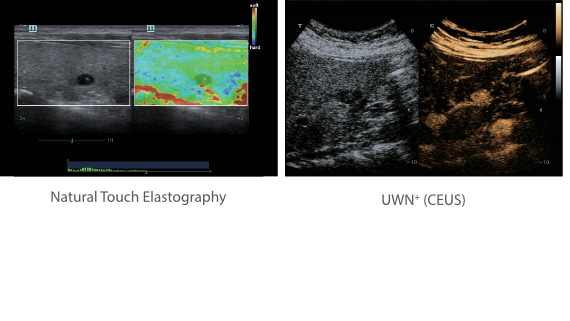

X-Insight adalah solusi untuk visualisasi lebih lanjut.

Sebagai mitra yang menyeluruh, DC-60 Exp dengan X-Insight memfokuskan dirinya untuk menghadirkan solusi yang komprehensif untuk membantu Anda mengelola semua aspek praktik klinis harian dengan mudah dan baik.

Dengan pemahaman mendalam atas kebutuhan pelanggan, DC-60 Exp dengan X-Insight dirancang untuk menyajikan efisiensi tinggi dengan pencitraan yang presisi, yang didukung oleh eXpress Clarity, eXceptional Intelligence, dan eXceeding Experience.